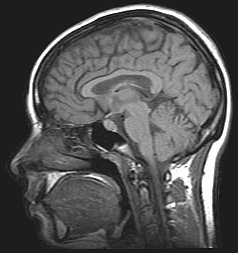

MRI brain

MRI of a human brain

The performance of Stroop and Simon tasks were monitored on 10 healthy young adults using magnetic resonance image (MRI) scanning.[38] Functional images were acquired at specific time intervals during each subject's scan.[38] Brain activation during the Stroop and Simon task was remarkably similar including anterior cingulate, supplementary motor cortex, visual association cortex, inferior temporal cortex, inferior parietal cortex, inferior frontal cortex, dorsolateral prefrontal cortex, and caudate nuclei.[38] Interference effects in the Stroop and Simon tasks activate similar brain regions at similar time distributions.[38]